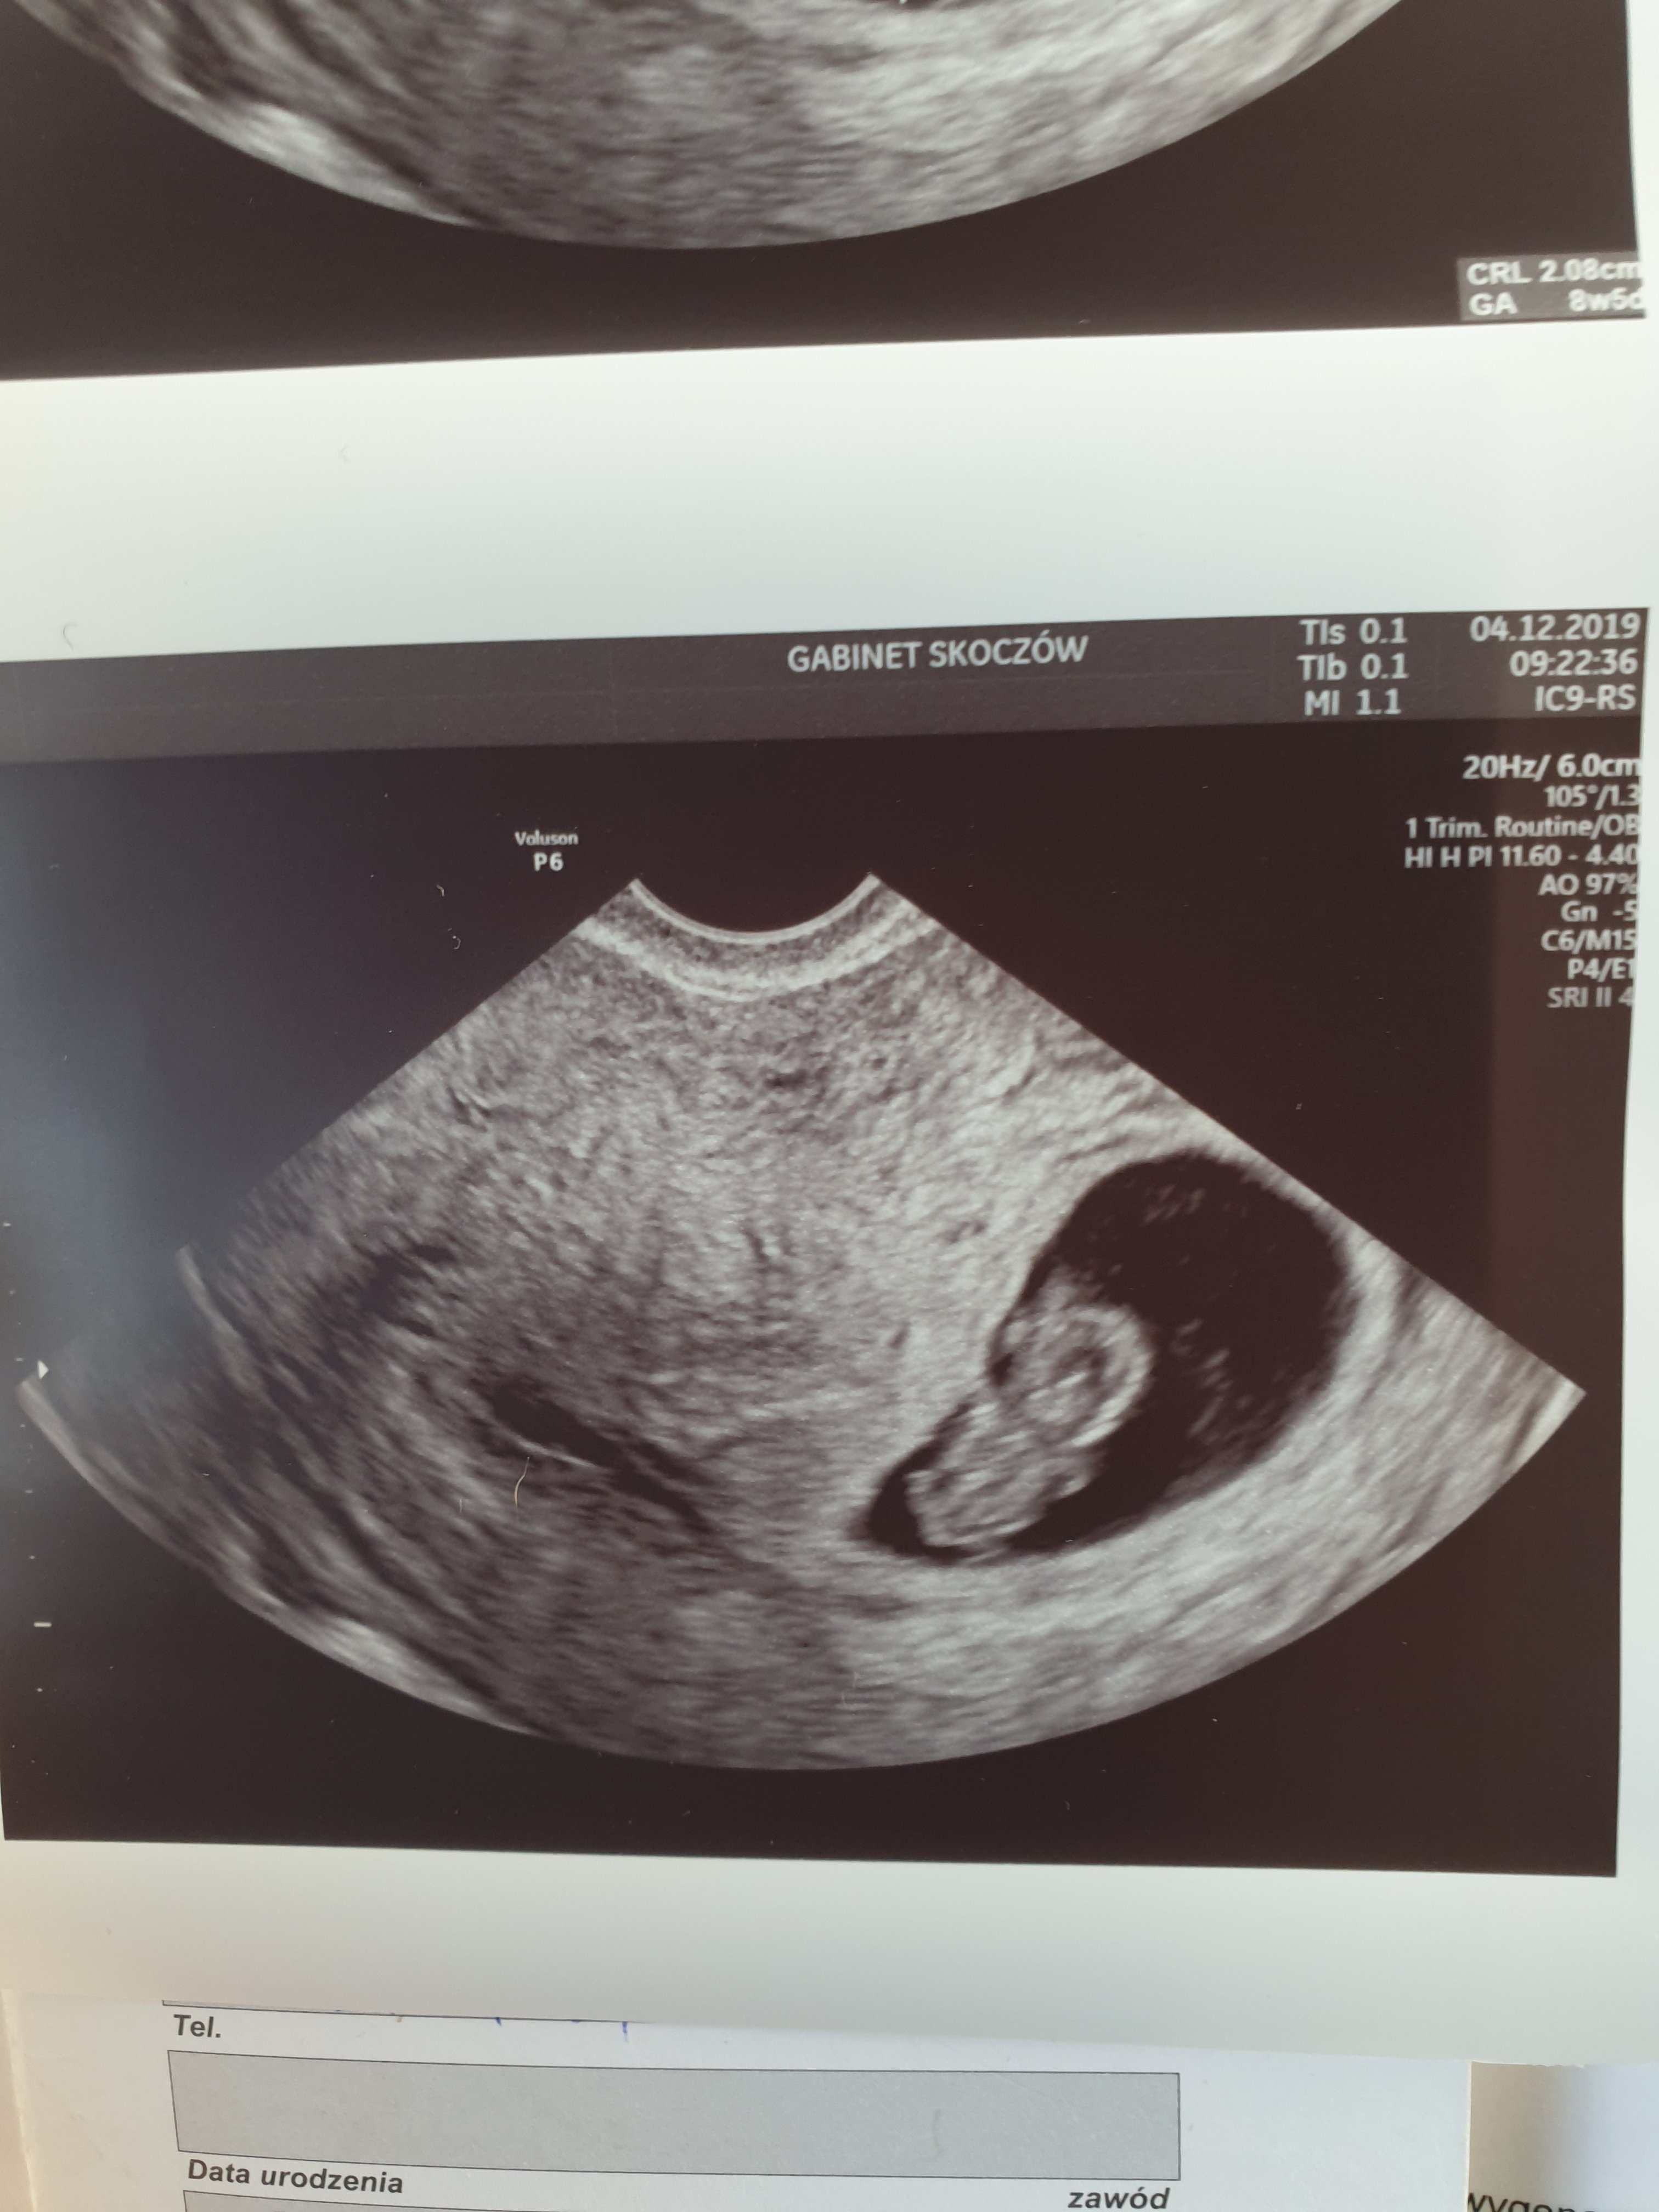

To tak się sprawy mają 🥰🥰

Gratulacje nowy mamusią

A aktualnym spokojnej ciąży

Załączniki

• 20191204_111527.jpg

20191204_111527.jpg

825,9 KB · Wyświetleń: 121

• 20191204_111534.jpg

20191204_111534.jpg

807,7 KB · Wyświetleń: 124

Hmm mi z flo wychodzi 9td4 mija się z usg około 2 dni wiec jest super ale mierząc powiedziała mi 2 cm wszystko Oki rączki nóżki główka serduszko heh i dupcia bo akurat tak się ustawiło